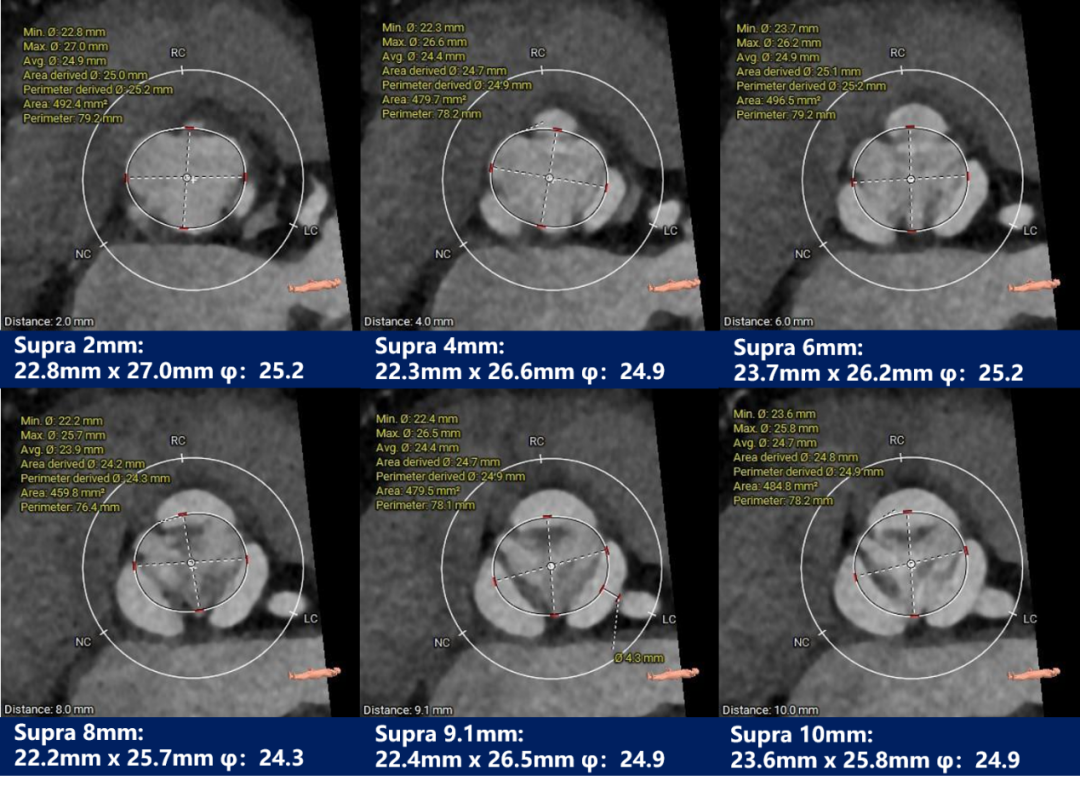

瓣上测量

瓣上测量:瓣叶基本无钙化,有明显增生肥厚。